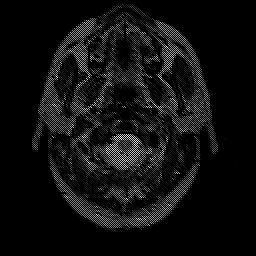

glioma overlay -- Slice #1

[Home][Help][Clinical] Slice 1